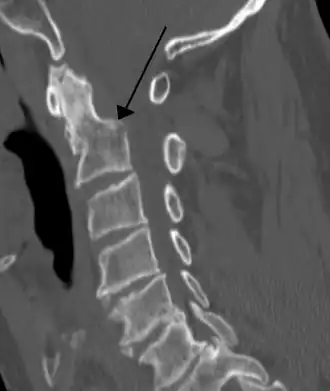

Imagerie

- Rachis cervical de profil : est le cliché de loin le plus utile ; il doit permettre la visualisation de l’occiput au disque C7 –D1[3]. Dans le cas contraire, il faut le refaire. Chez certains patients au cou court, la visualisation de C7 – D1 est impossible. On réalise un cliché dans la position du nageur, mais on court le risque de déplacer une lésion instable[3], et surtout en cas de contexte clinique évocateur (douleur, troubles neurologiques) on passe directement au scanner de la charnière cervico-dorsale[3] ;

Les clichés de rachis cervical sont difficiles à interpréter. Un cliché interprété comme normal peut se révéler pathologique après relecture lorsqu’on recherche une anomalie précise. Un cliché normal et relu comme tel n’élimine pas la présence d’une lésion osseuse ou des parties molles découverte sur des clichés ultérieurs[3]. Cependant, les lésions instables du rachis cervical présentant des risques neurologiques sont visibles sur les clichés initiaux après lecture sérieuse avec un minimum de soin. Le cliché initial de rachis cervical de profil doit permettre d’éliminer un risque de survenue de lésion neurologique s’il est lu correctement. En cas de doute diagnostic, le scanner dont le niveau est orienté par les radiographies est l’examen de choix[3].

Cliché de profil

de loin le plus important. Sur ce cliché on apprécie :

- la régularité des 7 lignes repères longitudinales :

- Espace clair pré vertébral,

- Alignement du bord antérieur des corps,

- Parois postérieures des corps,

- Bord antérieur des massifs articulaires,

- Bord postérieur des massifs articulaires,

- Limite postérieure du canal (bord antérieur des lames, bien visible),

- Alignement des extrémités des apophyses épineuses ;

- la régularité de l’empilement des massifs articulaires sans découverture localisée, et la régularité de l’espacement inter épineux. Surtout, la conjonction des irrégularités à un même niveau fait fortement suspecter une lésion osseuse ou ligamentaire.

Il faut insister sur la détection d’un antélisthésis (déplacement d’un corps vertébral en avant sur le corps vertébral sous jacent) bien visible sur l’alignement des bords postérieurs des corps vertébraux. Un antélisthésis de plus de 2 mm en dessous de C4 et 4 mm au-dessus de C4 est pathologique chez l’adulte. La plupart des lésions osseuses s’accompagnent en règle d’un antélisthésis. Les associations de fractures à des niveaux différents sont fréquentes[3] et il faut les rechercher systématiquement.